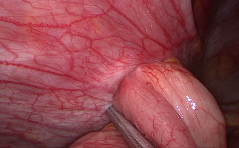

Der spezielle Fall

Ein ungemütlicher Endometriumpolyp PDF Dokument